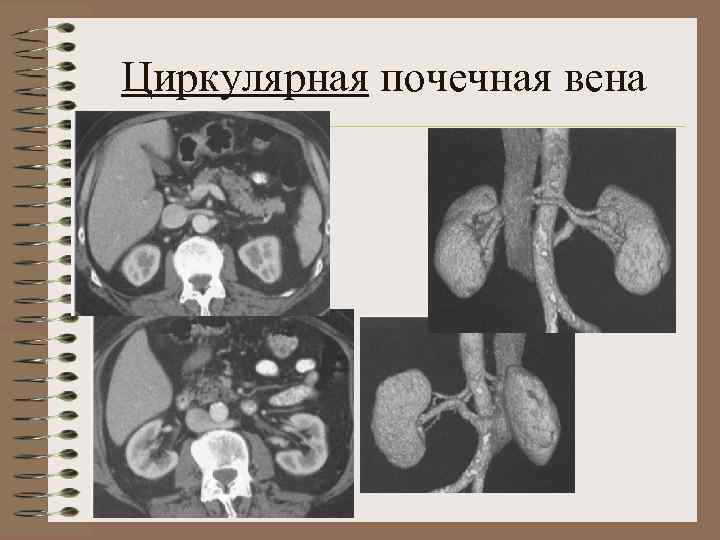

Аномалии почечных вен • А. аномалии правой почечной вены (множественные вены, впадение яичковой вены в почечную) • Б. аномалии левой почечной вены кольцевидная вена, ретроаортальная, экстракавальное впадение

Добавочная почечная артерия Ранее деление почечной артерии Кольцевидная почечная вена Множественные почечные вены Правая НПВ

Циркулярная почечная вена